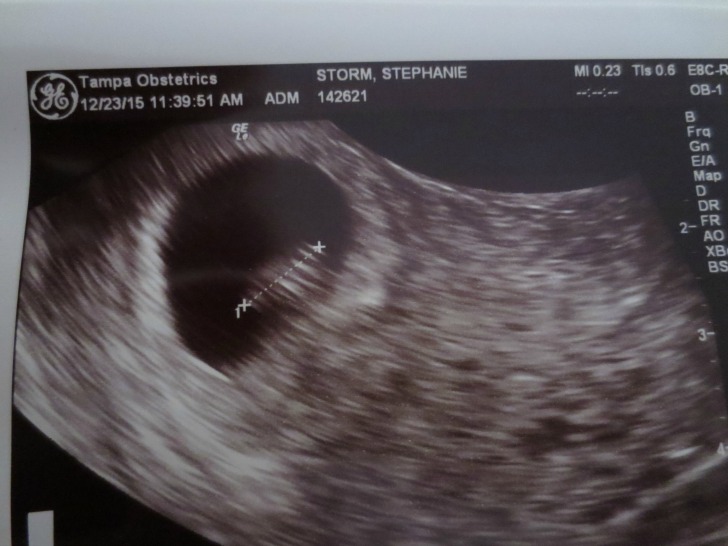

6+5 weeks, transvaginal

Transvaginal is a true image and transabdominal is mirrored.